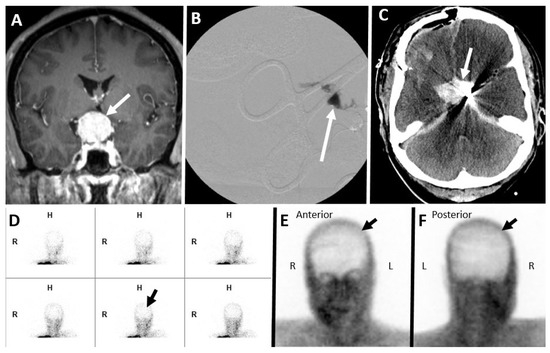

7.1. Nuclear Scintigraphy

7.8. Magnetic Resonance Angiography (MRA) Brain